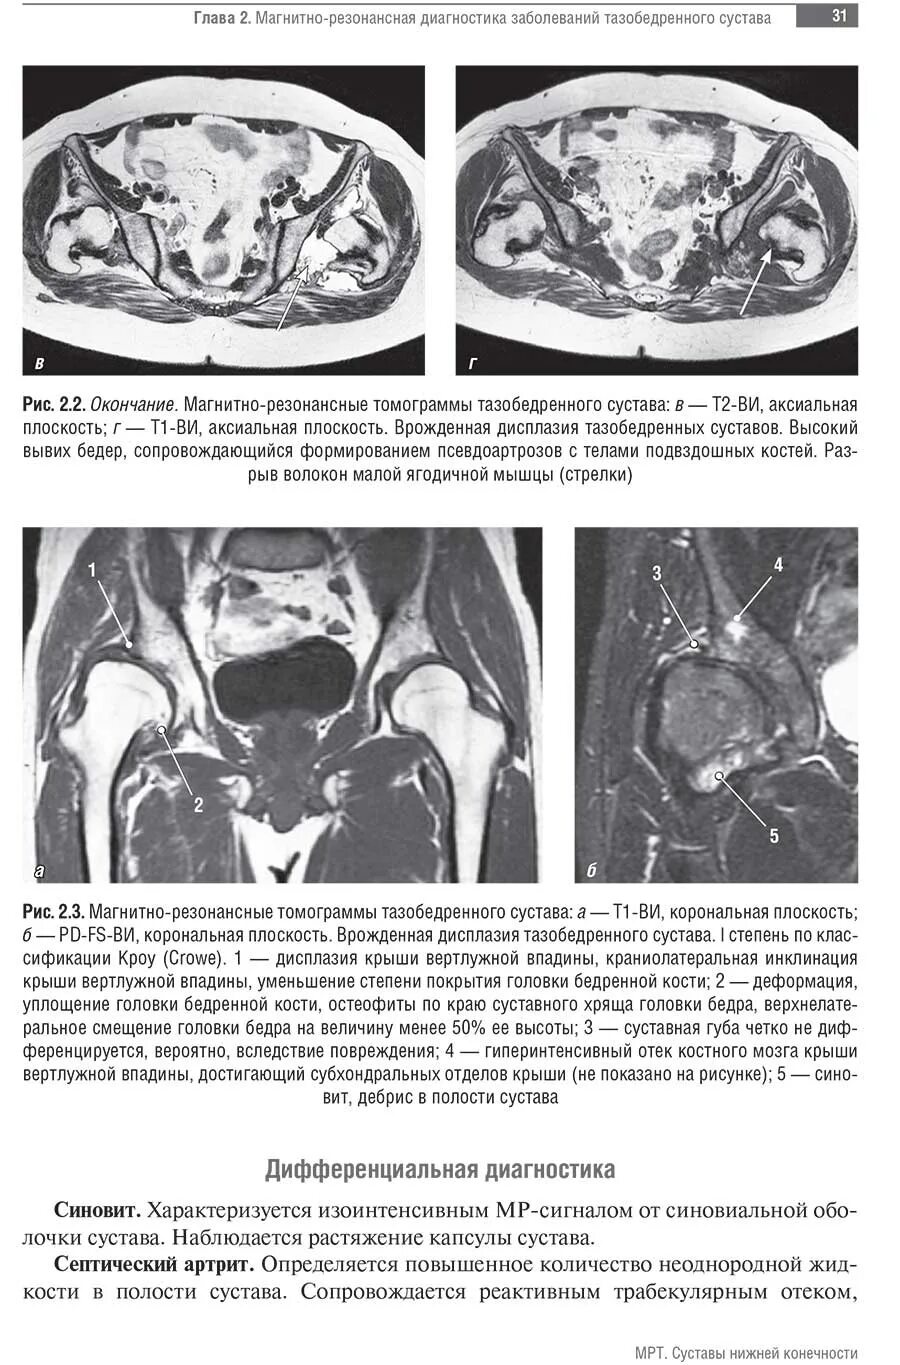

Мрт суставов кемерово